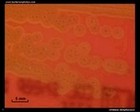

Staphylococcus aureus micrograph (Gram stain) |

Staphylococcus aureus Gram stain |